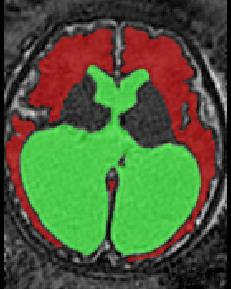

Limiting failures of machine learning systems is of paramount importance for safety-critical applications. In order to improve the robustness of machine learning systems, Distributionally Robust Optimization (DRO) has been proposed as a generalization of Empirical Risk Minimization (ERM). However, its use in deep learning has been severely restricted due to the relative inefficiency of the optimizers available for DRO in comparison to the wide-spread variants of Stochastic Gradient Descent (SGD) optimizers for ERM. We propose SGD with hardness weighted sampling, a principled and efficient optimization method for DRO in machine learning that is particularly suited in the context of deep learning. Similar to a hard example mining strategy in practice, the proposed algorithm is straightforward to implement and computationally as efficient as SGD-based optimizers used for deep learning, requiring minimal overhead computation. In contrast to typical ad hoc hard mining approaches, we prove the convergence of our DRO algorithm for over-parameterized deep learning networks with ReLU activation and a finite number of layers and parameters. Our experiments on fetal brain 3D MRI segmentation and brain tumor segmentation in MRI demonstrate the feasibility and the usefulness of our approach. Using our hardness weighted sampling for training a state-of-the-art deep learning pipeline leads to improved robustness to anatomical variabilities in automatic fetal brain 3D MRI segmentation using deep learning and to improved robustness to the image protocol variations in brain tumor segmentation. Our code is available at https://github.com/LucasFidon/HardnessWeightedSampler.